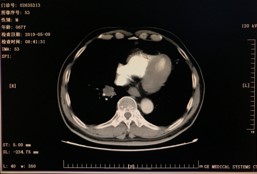

2019年3月-2019年4月 伊立替康+卡培他滨方案化疗2周期。(伊立替康180mg d1,8 卡培他滨1500mg bid,3周重复)

病理检查结果:(骶前转移、左侧腰大肌旁转移:SD(略减小)

右肺转移:PD